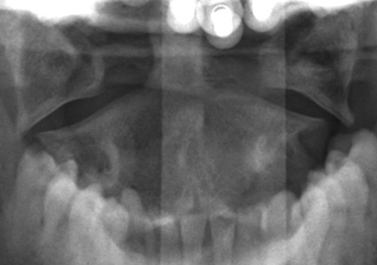

3. Pseudo-Jefferson’s fracture

Psuedo-Jefferson’s fracture or pseudospread of the atlas on the axis refers to the normal overhang of the lateral masses of C1 over the lateral edges of the body of C2. This is a normal physiologic finding in children up to the age of 7, most likely due to differential speed of growth of the atlas versus the axis.4 6-mm of overhang is the accepted maximal value of normal overhanging when adding the offset of the sides bilaterally.